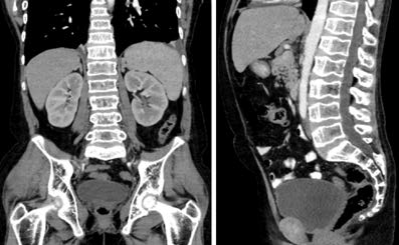

Cortisol sérico: 2,07 μg/dL (bajo) y ACTH: 37 pg/mL (normal-elevado); valores que fueron corroborados posteriormente en el ámbito ambulatorio, con cortisol sérico: 18 μg/dL y ACTH: 10 pg/mL normales, descartándose así insuficiencia adrenal asociada. Aldosterona sérica normal y actividad de renina plasmática detectable. Ecografía Doppler de arterias renales sin evidencia de estenosis, con flujo intraparenquimatoso renal normal. Tomografía de abdomen y pelvis con hallazgos superponibles a los ecográficos, ausencia de útero y anexos, no se logran visualizar rudimentos gonadales (figura 2).

Tomografía axial computarizada de abdomen (contrastada), se evidencia la ausencia de genitales femeninos internos

Figura 2: Tomografía axial computarizada de abdomen (contrastada), se evidencia la ausencia de genitales femeninos internos

Fuente: historia clínica (con permiso)